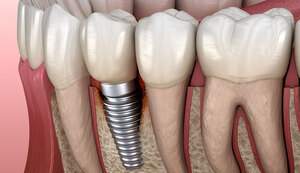

インプラントとは、虫歯や歯周病などの様々な原因により歯が失われてしまったところへ、人工の歯の根=人工歯根(インプラント)をつくり、その上に被せ物を装着する治療法のことです。

インプラントの特徴は、歯根まで再現し骨とインプラントが直接結合することにより、天然歯と同じような見た目・機能の両面において元の自然な状態へ近づくことができ、またしっかり噛むことができます。

インプラントの構造は、上部構造・アバットメント部(支台部)・歯根部の3つの構造から成り立っています。

上部構造は、いわゆる被せものを指しており、歯の部分です。

アバットメント(支台部)は、上部構造と歯根部をつなぐ役割を果たしています。

歯根部は、チタン製で、この部分と顎の骨が結合します。

インプラント歯根部のチタンが骨と結合する確率は、95%と高い確率となっています。